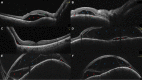

Purpose: To study the incidence and characteristics of bacillary layer detachment (BALAD) occurring with the two most common choroidal malignancies, choroidal metastasis and choroidal melanoma.

Methods: A retrospective multicentric record analysis. Eyes with a diagnosis of choroidal melanoma or choroidal metastasis that had good-quality fundus photography and spectral domain optical coherence tomography (OCT) scans of the macular and tumor regions allowing for delineation of the retinal layers were included for analysis. Qualitative image evaluation was done by two independent graders for the presence, location, and OCT features of BALAD, as well as any associated intraretinal or subretinal fluid. Demographic and clinical data were also retrieved.

Results: Of the 11 eyes with choroidal metastasis and 7 eyes with choroidal melanoma that were included in the final analysis, 6 (54.5%) and 1 (14.3%) had BALAD, respectively. The BALAD co-localized with the subretinal fluid in all cases and with the intraretinal fluid in 1/3 cases (33.3%), was foveal in location in 3 eyes (42.9%), was overlying the tumor in 6 eyes (85.7%), and varied in number and size. Reflectivity within the BALAD was consistently higher than the vitreous and adjacent subretinal fluid, and discernable suspended hyperreflective particles were noted in 5 eyes (71.4%).

Conclusion: BALAD is relatively common with choroidal metastasis. The OCT features described supplement our recognition of this new entity.